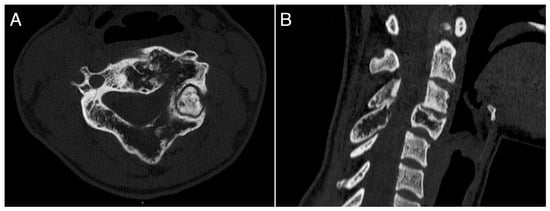

A 26-year-old female with a massively lytic lesion in C4 showed consistent ossification after seven months of treatment (Figure 2 and Figure 3). She chose to discontinue denosumab after 20 administrations due to being asymptomatic and being at her fertile age. However, ten months after stopping the medication, she experienced severe neck and upper left pain, leading her to seek urgent medical attention at the emergency department of our clinic. CT and MRI showed a local recurrence of the ABC in C4 (Figure 4 and Figure 5). She then received a “re-challenge” treatment with denosumab according to the above-mentioned protocol, and the treatment is still ongoing. At the last follow-up, 20 months after being on denosumab with a monthly schedule, the patient was asymptomatic, and the last CT showed good ossification of C4 (43 months follow-up from the first treatment).

Figure 4. CT scan showing a local recurrence occurring ten months after stopping denosumab treatment. (A): axial view; (B): sagittal view.